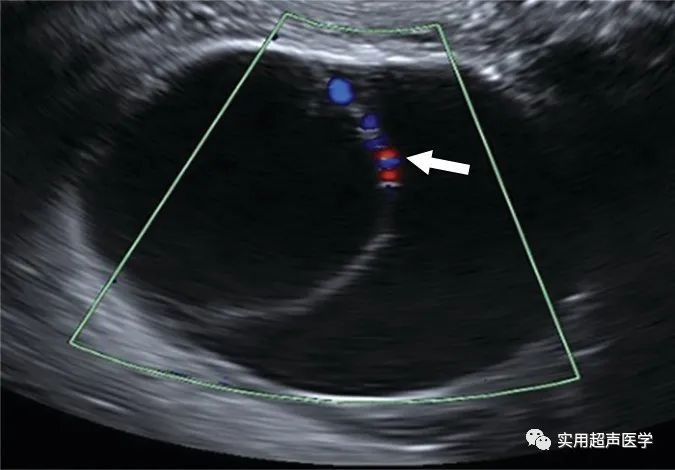

46岁女性,因粘液性囊腺瘤导致盆腔胀满。彩色多普勒超声图像显示右侧卵巢单房囊肿,内壁不规则(箭头)与卵巢-附件报告和数据系统 (O-RADS) 3 类病变一致。壁不规则不会突出囊腔超过 3 mm,因此不符合实性成分或状突起的标准。